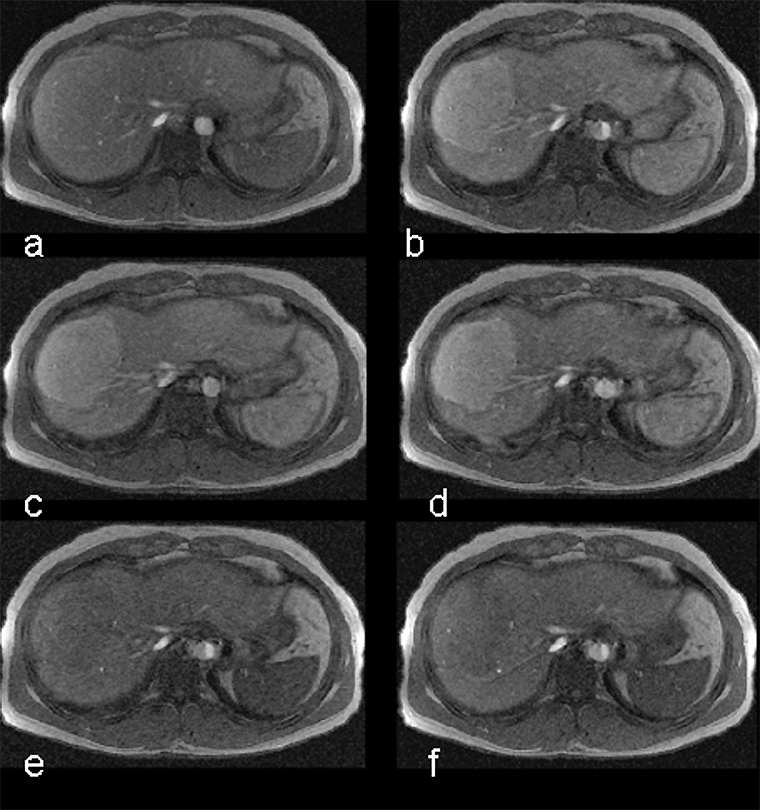

Manganese also has an affinity for the myocardium and can act as biomarker in heart disease. Manganese ions compete with calcium for entry into cardiac cells. There the ions bind to macromolecules and influence the relaxation of cell and tis­sue water. Heart diseases gradually inactivate calcium transport mechanisms due to lower metabolic activity. Thus, manganese uptake is reduced accordingly; man­ga­nese-induced changes of tissue relaxation reflect tissue calcium homeostasis and thus myocardial viability (Figures 13-17 and 13-18) [⇒ Skjold 2004, ⇒ Skjold 2007] and allows the assessment of stunned and viable myocardium [⇒ Spath 2021, ⇒ Singh 2023].

Figura 13-17:

Mn-DPDP: A short axis single shot IR Turbo-FLASH image of a heart before contrast agent application (top), and another image of the same heart with the same parameter settings one hour after the end of the contrast agent infusion (bottom).

To the right of each image sectoral divisions of the left ventricle are shown, depicting R1 color maps of the respective slice. The left ventricle shows a marked change in contrast (modified from Skjold 2004).

Figura 13-18:

Follow-up of a cardiac infarction. Manganese-enhanced myocardium (Mn-DPDP, man­ga­fo­di­pir) showing an infarcted region in the lateral wall of the left ventricle (dark wall region).

(Image courtesy of Dr. Arne Skjold, Trondheim, Norway).